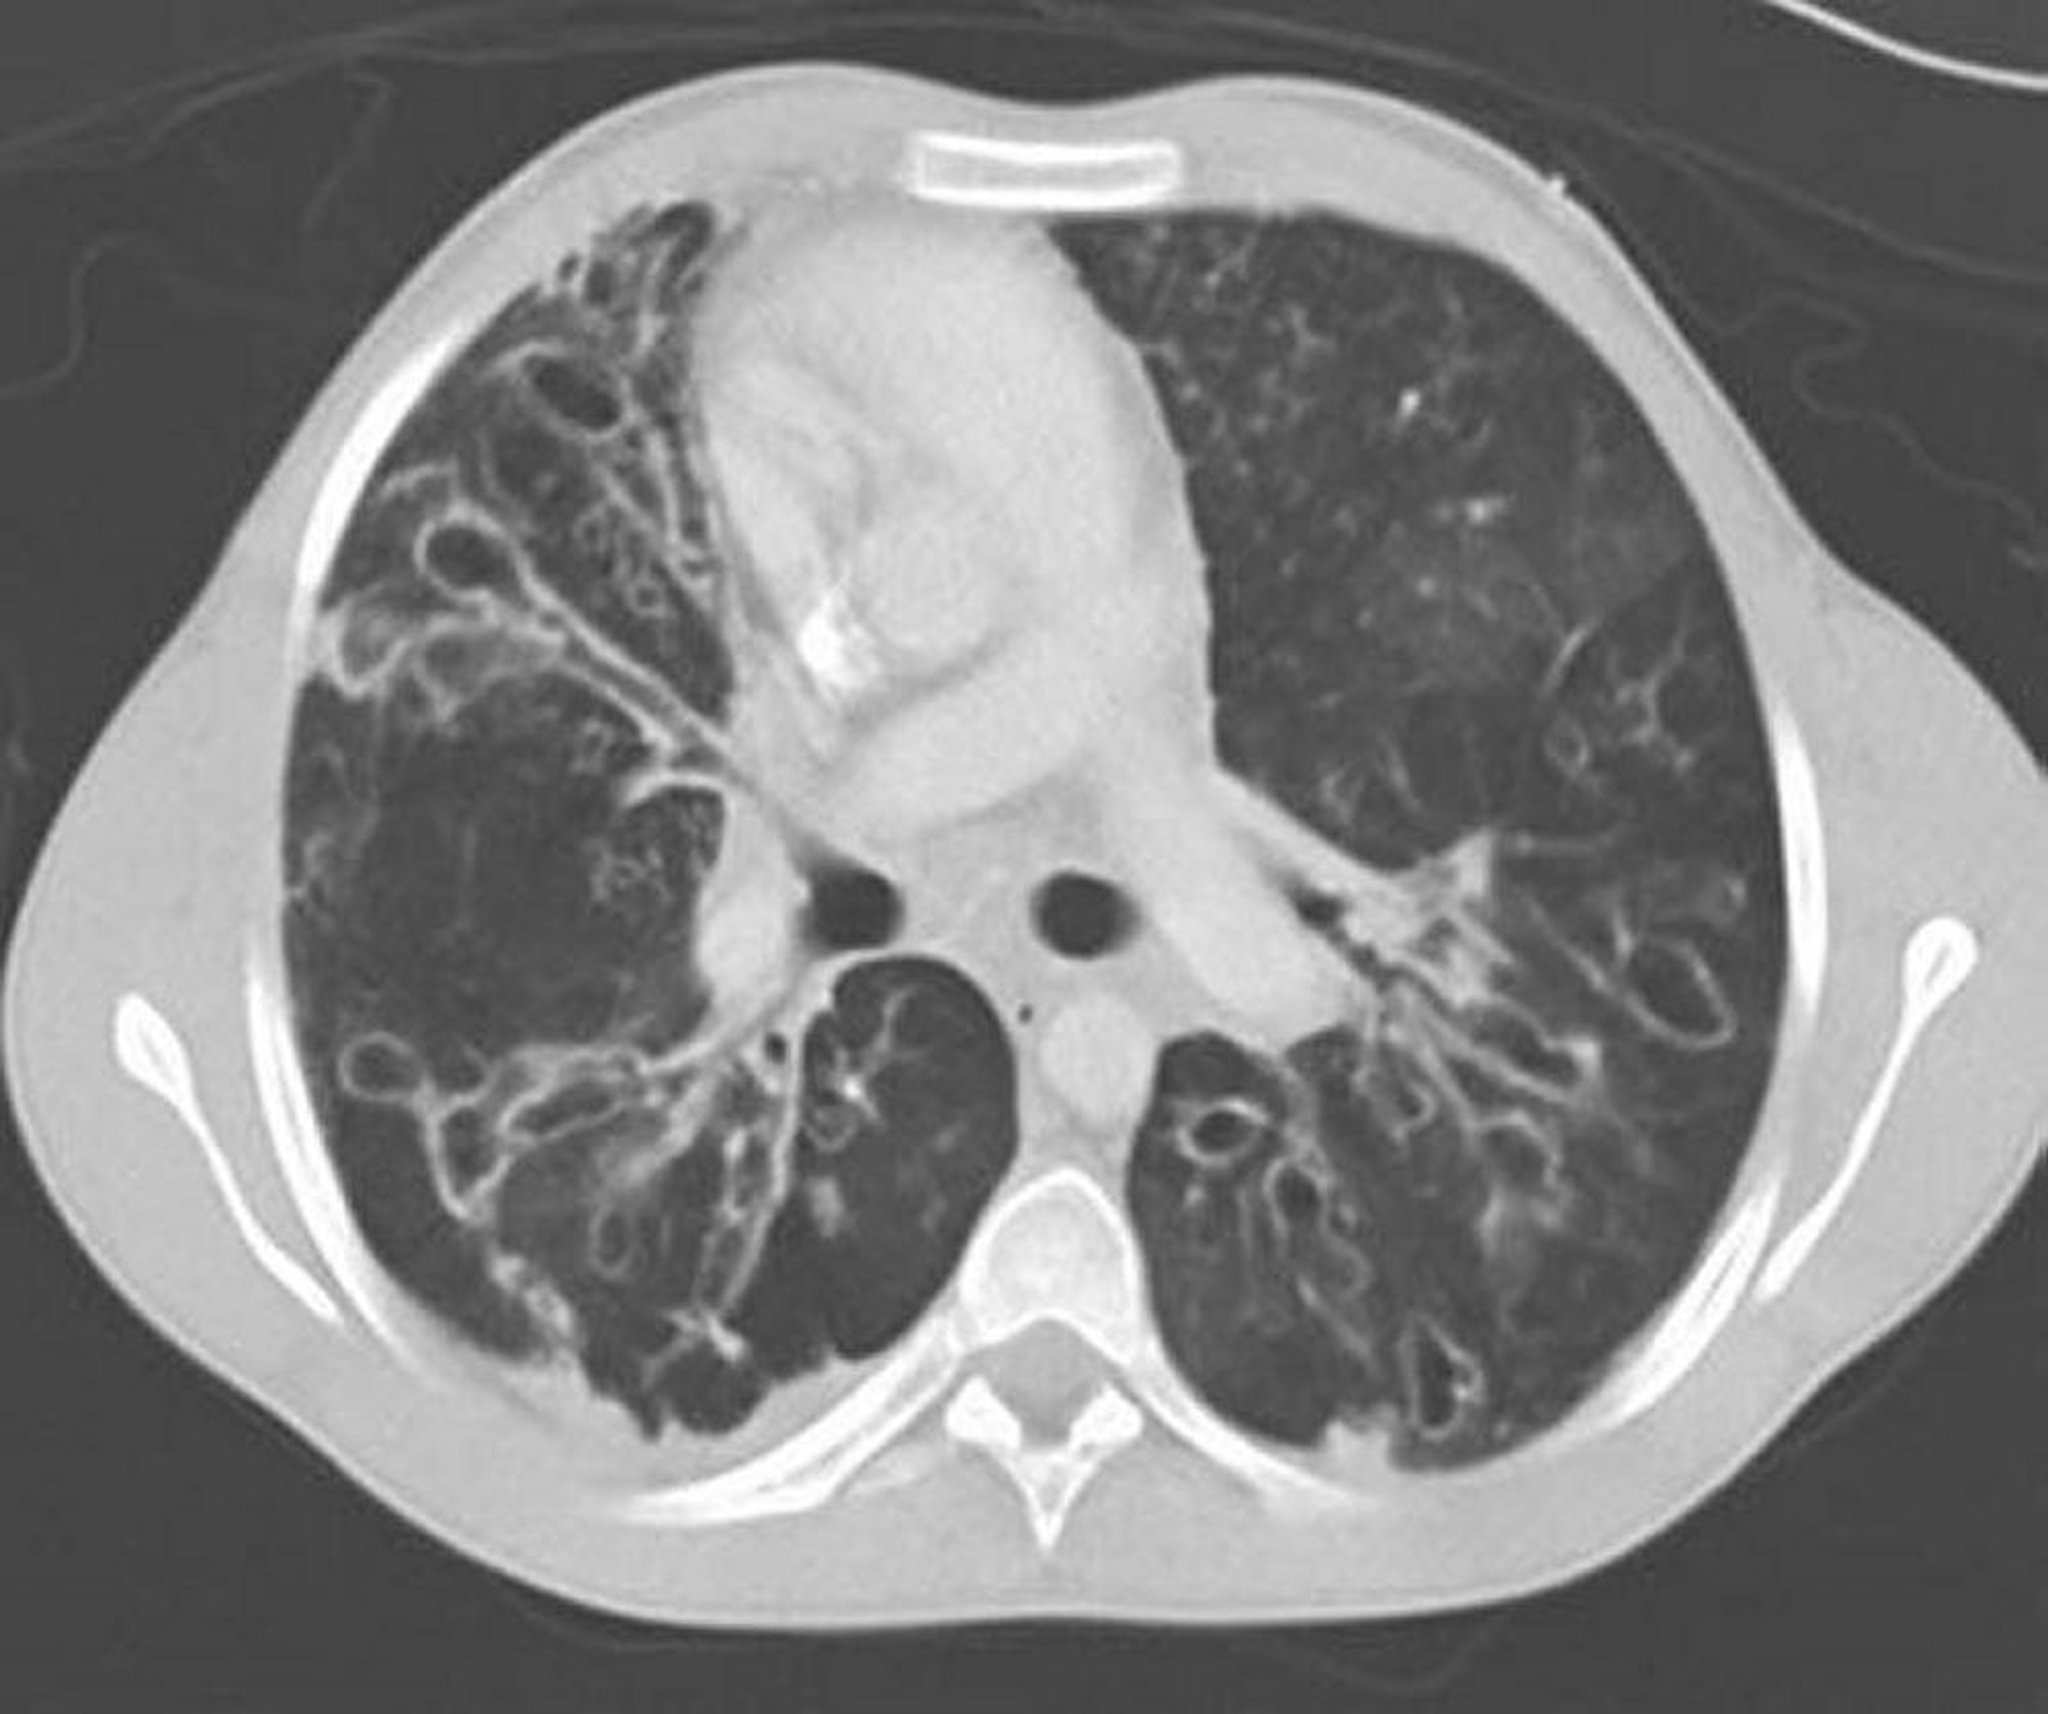

Allergische bronchopulmonale Aspergillose (Bronchiektasie)

Ein kontrastverstärktes CT des Thorax zeigt schwere Bronchiektasen in den mittleren Lungenbereichen mit stark erweiterten und ektatischen Atemwegen und zystischen Veränderungen. Die Ektasie der Atemwege ist durch ein Verhältnis von Atemwegen zu angrenzenden Gefäßen > 1 gekennzeichnet.

By permission of the publisher. From Coakley R, Boucher R, Fiel S, et al. In Bone's Atlas of Pulmonary and Critical Care Medicine. Edited by J Crapo. Philadelphia, Current Medicine, 2005.